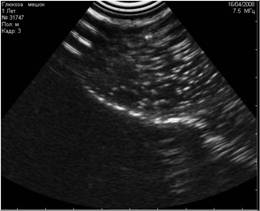

![]() |

Рис. 9. Истинные эхоакустические тени, возникающие позади конкрементов в мочевом пузыре. |

Рис. 10. А вот и сами камни. |